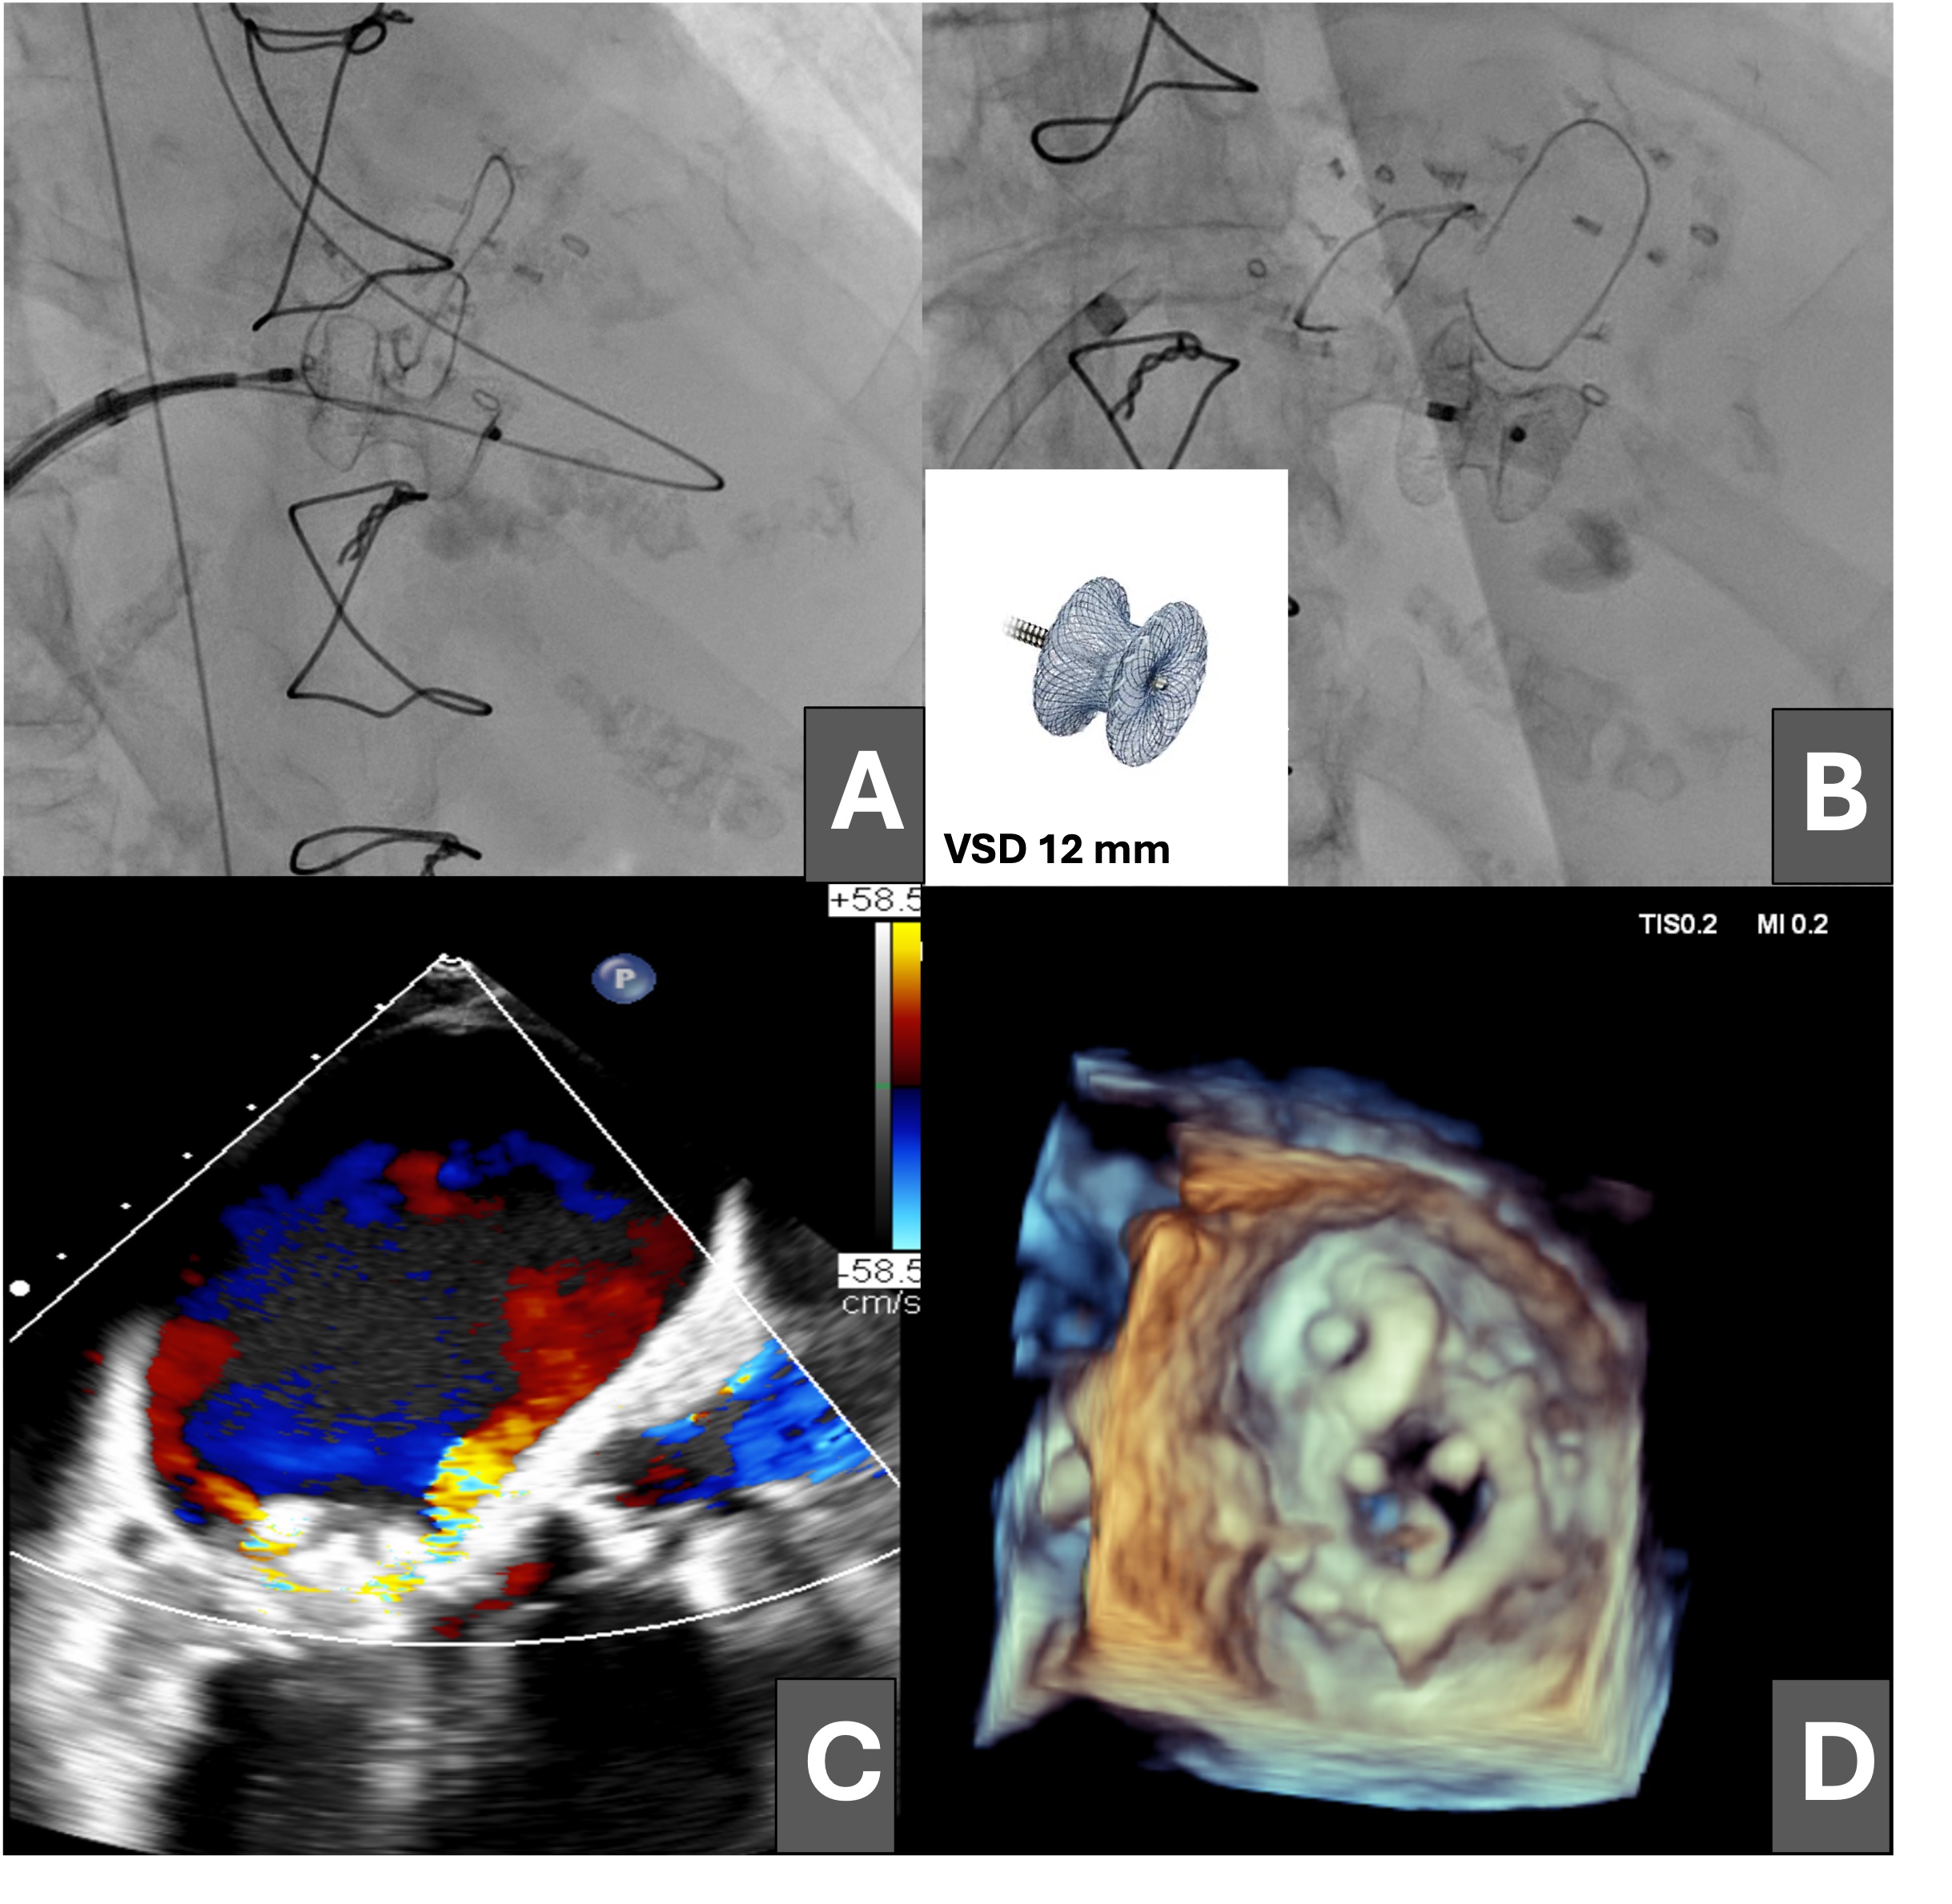

Finally, a 12-mm ventricular septal defect (VSD) closure device was advanced (Figure 3A and B) and released with adequate compression, resulting in moderate residual mitral regurgitation as shown on transesophageal echocardiography (Figure 3C and D; Videos 3 and 4).

In select high‑risk patients with large, early postoperative mitral PVL not amenable to dedicated PVL devices, the off‑label use of a VSD occluder may provide a feasible alternative. Careful imaging, valve‑prosthesis compatibility assessment, and multidisciplinary decision making are paramount.